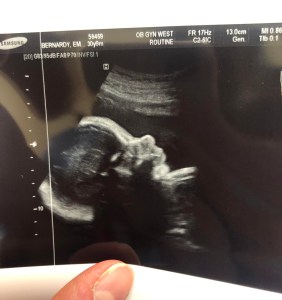

At my 28-week appointment, I mentioned to my OB how many individuals have commented on my “small belly” or how they “can barely even tell I am pregnant.”  Even my primary care physician at my annual physical a few days prior made a comment saying “wow, you’re still so tiny for being in your third trimester!”  While I know that no one means this in a malicious way, and perhaps they even intend for it to be a compliment, it still upsets me and makes me feel like I am doing something wrong.  My OB told me that my belly is measuring within the normal limits, and my weight gain is appropriate for my weeks of gestation as well.  He then offered for me to have an ultrasound to confirm what he already knew to be true – that the baby was healthy.  He stated that he saw no medical reason which would warrant the need for the ultrasound, but if it would help me to feel better about the comments coming my way and reaffirm that our child is indeed growing appropriately, he would happily arrange for it.  I jumped at the opportunity, and spent the next twenty minutes admiring our beautiful, healthy baby.  The reason I share this is so everyone can be cognizant of how they speak to a woman who is expecting a child.  We all know that humans come in many shapes, sizes, and colors, and similarly, no pregnant woman (even from one pregnancy to her next) will look exactly the same as another.  As Psalm 139:14 reads so beautifully: “I will praise thee, for I am fearfully and wonderfully made.”

profile

I fall more in love with you every day, little B.